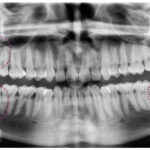

Un niño generalmente tiene 20 dientes de leche, también conocidos como muelas temporales. Estos dientes comienzan a aparecer alrededor de los 6 meses de edad y se completan aproximadamente a los 2-3 años.

Un niño de 11 años generalmente tiene 28 dientes en total, incluyendo tanto los dientes de leche como los permanentes. Estos se dividen en 20 dientes de leche y 8 dientes permanentes. Por otra parte, también es común que a esta edad ya haya salido al menos una muela permanente, conocida como la primera molar permanente o «muela de los seis años.

A los 7 años, los niños suelen tener un total de 20 dientes de leche. Estos dientes están compuestos por 8 incisivos, que se encuentran en la parte frontal de la boca y son utilizados para cortar los alimentos; 4 caninos, que se localizan al lado de los incisivos y ayudan a desgarrar la comida; y 8 molares, que se ubican en la parte posterior de la boca y son responsables de triturar los alimentos.